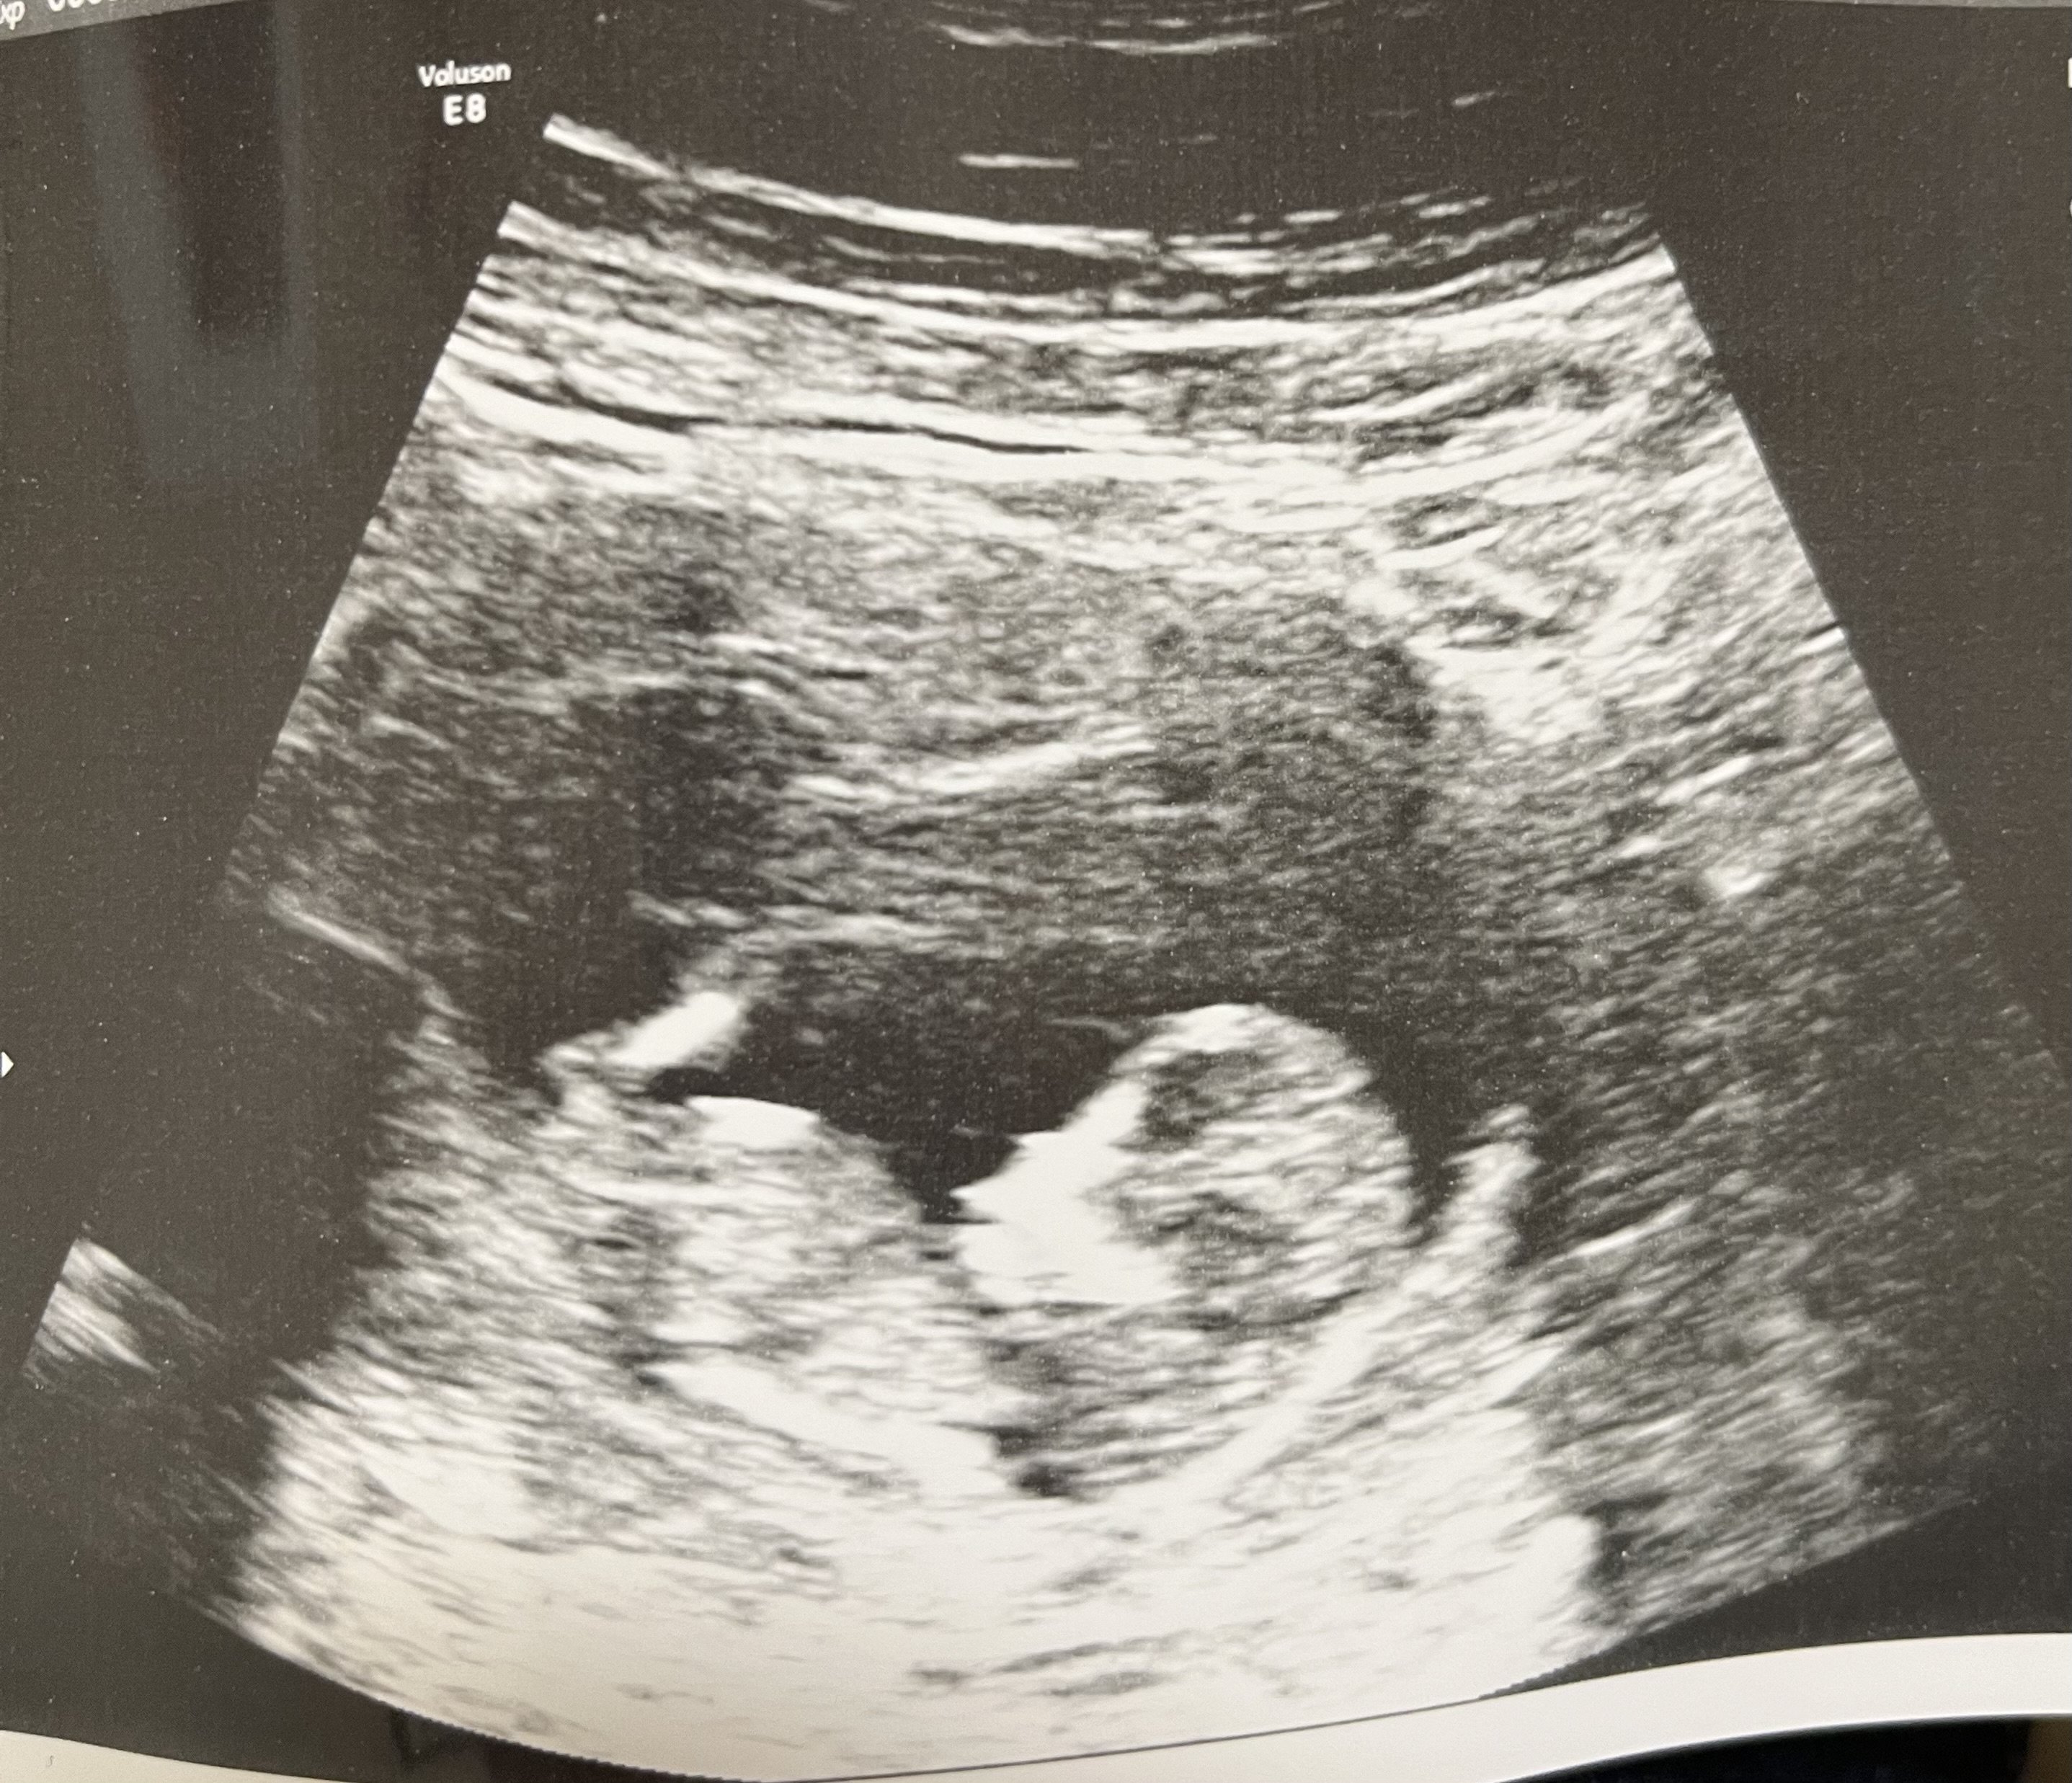

Big yawn, little girl! 20 weeks + 1 day (last Thursday) Estimated about 9 ounces, measuring about a week and a half behind after being right on track earlier in the pregnancy. Placental insufficiency, absent end-diastolic flow, growth restriction... but she was very active during the scan and that is very positive. We'll be doing another scan at 23 weeks and we'll see where we go from there.

Big yawn, little girl!

20 weeks + 1 day (last Thursday)

Estimated about 9 ounces, measuring about a week and a half behind after being right on track earlier in the pregnancy.

Placental insufficiency, absent end-diastolic flow, growth restriction... but she was very active during the scan and that is very positive. We'll be doing another scan at 23 weeks and we'll see where we go from there.